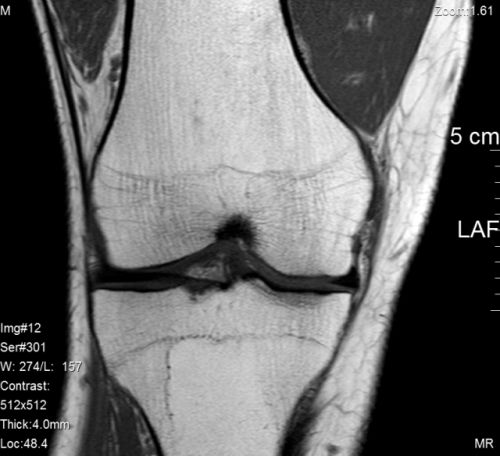

Darf ich vorstellen - mein rechtes Knie:

Da macht sich Erleichterung breit - Frau Dr. Orthopädin diagnostiziert heute nach dem MRT, dass mein Knie heile ist.

Ich habe es also - wie angenommen und gehofft - "nur" falsch be- bzw. überlastet.

Ich darf langsam anfangen wieder zu radeln.

Zitat: "Keine Berge, also nicht Gaustrasse hoch...."

Ich wusste gar nicht, dass da ein Berg ist.... ;) ;)

Die Aussage ist klar und unmissverständlich und nach dem zum Teil sehr schmerzhaften Affentheater nehme ich sie auch ernst:

Ernstzunehmende Höhenmeter fallen erst mal aus...

Aber gut, am Rheinufer und im Ried ist es ja auch schön...es gibt ja auch noch die Altrheinrunde... ;)

Ich bin heilfroh, dass das Knie heil ist und das ich überhaupt grünes Licht zum radeln habe.

Einschränkungen in der Streckenwahl nehme ich da ja (fast!) gern in kauf...